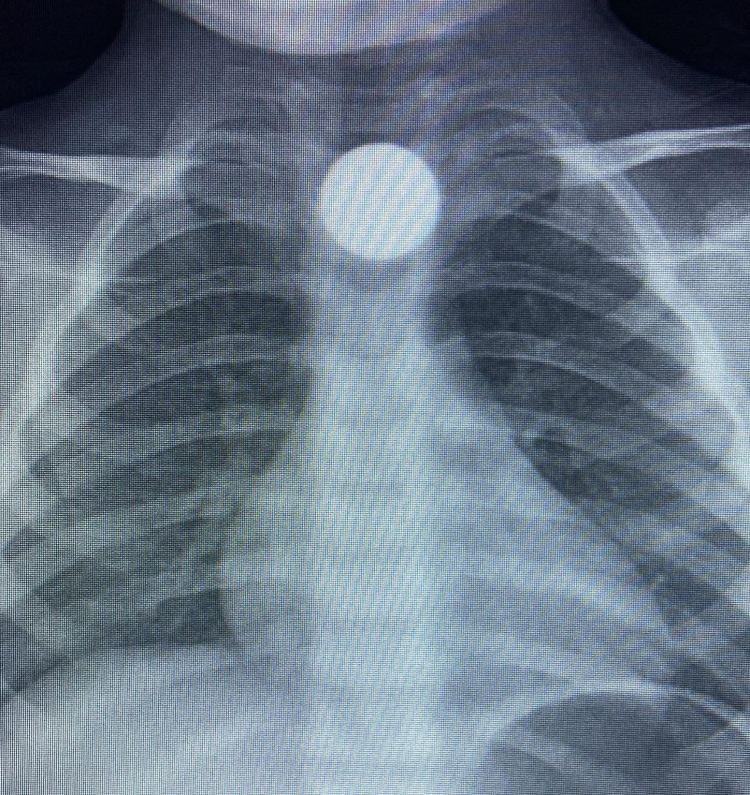

3 yaşındaki Bilal K., yerde bulduğu 50 kuruşluk madeni parayı ağzına atarak yuttu.

Yapılan incelemelerde, madeni paranın yemek borusunda takılı kaldığı belirlendi.

Küçük çocuk, ilk müdahalenin ardından ambulansla Bursa Yüksek İhtisas Eğitim ve Araştırma Hastanesi’ne gönderildi.